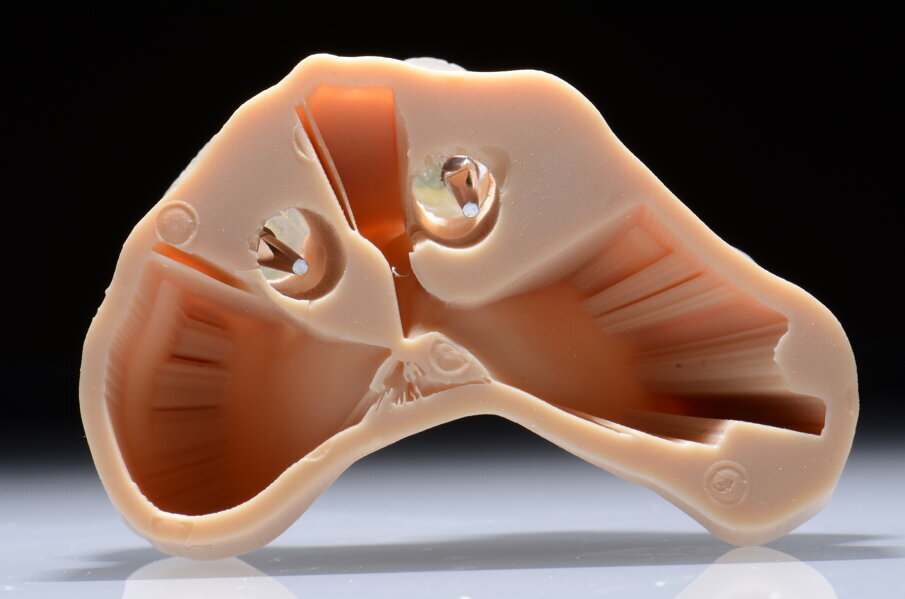

L’idea DIL (Digital Immediate Load) nasce da questa riflessione: se la dima viene alloggiata correttamente sul modello stereolitografico, e se la stessa viene utilizzata per inserire gli impianti allora possiamo pensare di utilizzare subito dopo il posizionamento implantare una seconda dima senza boccole (Sleeve) che chiameremo dima protesica. Subito dopo la chirurgia possiamo inserire attraverso gli spazi guidati i transfert da impronta sugli impianti e bloccarli con della resina alla dima stessa. In questo modo possiamo evitare di rilevare una nuova impronta (sia analogica che digitale) che ci costringerebbe a realizzare un nuovo modello e soprattutto a rilevare una nuova dimensione verticale specialmente nei casi di arcate edentule. Alla dima con i transfert bloccati vengono collegati gli analoghi. Questa unione tra dima protesica, transfert e analoghi degli impianti inseriti rappresenta il cuore della tecnica DIL. Infatti questo assemblato chirurgico-protesico viene riposizionato sul modello digitale master iniziale. Gli analoghi vengono a loro volta bloccati con della resina. Otteniamo così un modello master affidabile con la posizione corretta degli impianti (tecnica DIL). Questo tipo di approccio è stato in passato utilizzato con flussi analogici che avevano però un limite: il modello master ottenuto non era relazionabile all’antagonista e quindi si rendeva necessario un altro passaggio analogico per rilevare la nuova dimensione verticale8. Con la tecnica DIL, e quindi con un flusso tutto digitale il riposizionamento della dima protesica con i transfert sul modello master iniziale produrrà un modello master post chirurgico che avrà un duplice vantaggio, quello cioè di avere la posizione esatta degli impianti inseriti e quello di avere un’arcata già relazionata a quella antagonista (tecnica DIL). Sugli analoghi degli impianti, poi, vengono inserite le componenti secondarie scelte.

Alloggiamo la dima protesica (Fig. 33), e blocchiamo i transfert con della resina trasparente (tecnica DIL) (Figg. 34, 35). In questo modo possiamo far riposare il paziente in studio dopo appena 35 minuti dall’inizio dell’intervento. La dima protesica, infatti (Fig. 36) con i transfert inseriti viene completata con l’unione degli analoghi ai transfert (Fig. 37). L’insieme così composto viene riadattato sul modello master digitale iniziale (Figg. 38-40) sul quale era stata costruita sia la dima chirurgica che la dima protesica come anche il provvisorio. Gli analoghi vengono bloccati sul modello con resina trasparente (Figg. 41-43). Alloggiamo il provvisorio sul modello master digitale così ottenuto (Figg. 44, 45).

Fig. 41 - Resina trasparente e analoghi bloccati.

Fig. 42 - Finestre d’ispezione.

Fig. 43 - Analoghi bloccati sul modello master iniziale.

Il risultato sarà quello di ottenere un modello master già relazionato all’arcata antagonista e soprattutto un modello che contiene la posizione esatta degli impianti appena inseriti. Questo rappresenta il cuore della tecnica DIL, evitiamo impronta post-chirurgica, evitiamo la registrazione di una nuova dimensione verticale e realizziamo il modello di lavoro in pochissimo tempo.